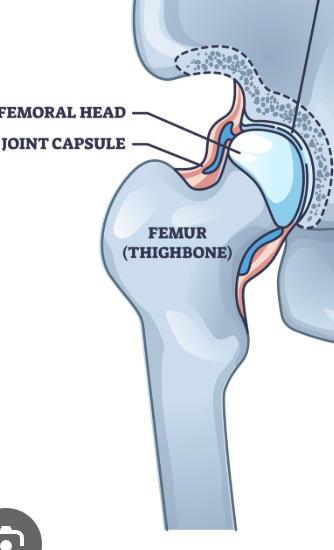

Acetabular labrum

Fibrous joint capsule